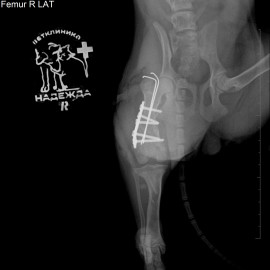

Обратились в нашу клинику из города Боровичи с щенком Джек-Рассел-Терьера по кличке Джесси. Щенка сбил велосипед, после чего она перестала наступать на правую заднюю лапу. После рентгенологического исследования был поставлен диагноз - перелом правого бедра. Проведена операция: остеосинтез правого бедра.

Снимок 2 после операции.